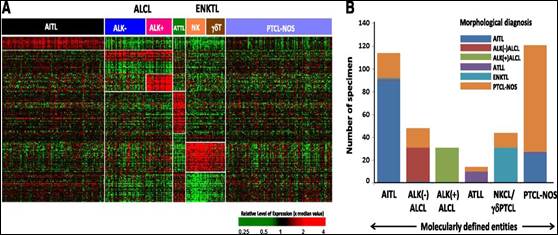

Los LNH-T conllevan un gran desafío al diagnóstico y al tratamiento. Teniendo en cuenta esta dificultad diagnóstica, en el 2014 se publicó una revisión de 131 casos de LNH-T cuyos diagnósticos habían sido revisados por un grupo de expertos en centros de referencia del National Comprehensive Cancer Network. La concordancia diagnóstica fue de 44%. El índice de discordancia entre los LNH-T periféricos NOS, AILTL, LNH-T anaplásico ALK – y LNH-T anaplásico ALK+ fue de 19%, 33%, 35% y 19% respectivamente.

Los autores concluyen que debido a la complejidad anatomo-patológica y molecular, los pacientes se benefician de una revisión de los preparados del diagnóstico, realizada por expertos(1).

Esta diferencia al diagnóstico es relevante ya que los diferentes subgrupos representan sobrevidas globales diferentes y, en algunos casos, una modificación en el tratamiento(2).

Estudios aún más

recientes evidencian la diferencia de expresión génica entre los diferentes

subtipos histológicos y, nuevamente, una discordancia notable entre el

diagnóstico realizado por inmunohistoquímica y aquél definido por su perfil

molecular (Figura 2)(3)![]() .

Figura 2. Discordancia entre el diagnóstico realizado por inmunohistoquímica y el definido por perfil molecular